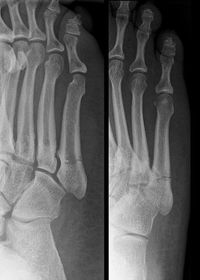

Describe the alignment of metatarsal 2 | There is no angulation nor displacement of the distal segment relative to the proximal segment. |

Describe the alignment of metatarsal 3 | The distal segment is displaced laterally (50% apposition) and angulated medially. |

Describe the alignment of metatarsal 4 | The distal segment is displaced laterally (75% apposition) but there is no apparent angulation. |

Describe the tubulation of the metatarsals | Metatarsals are overtubulated - decreased girth. |